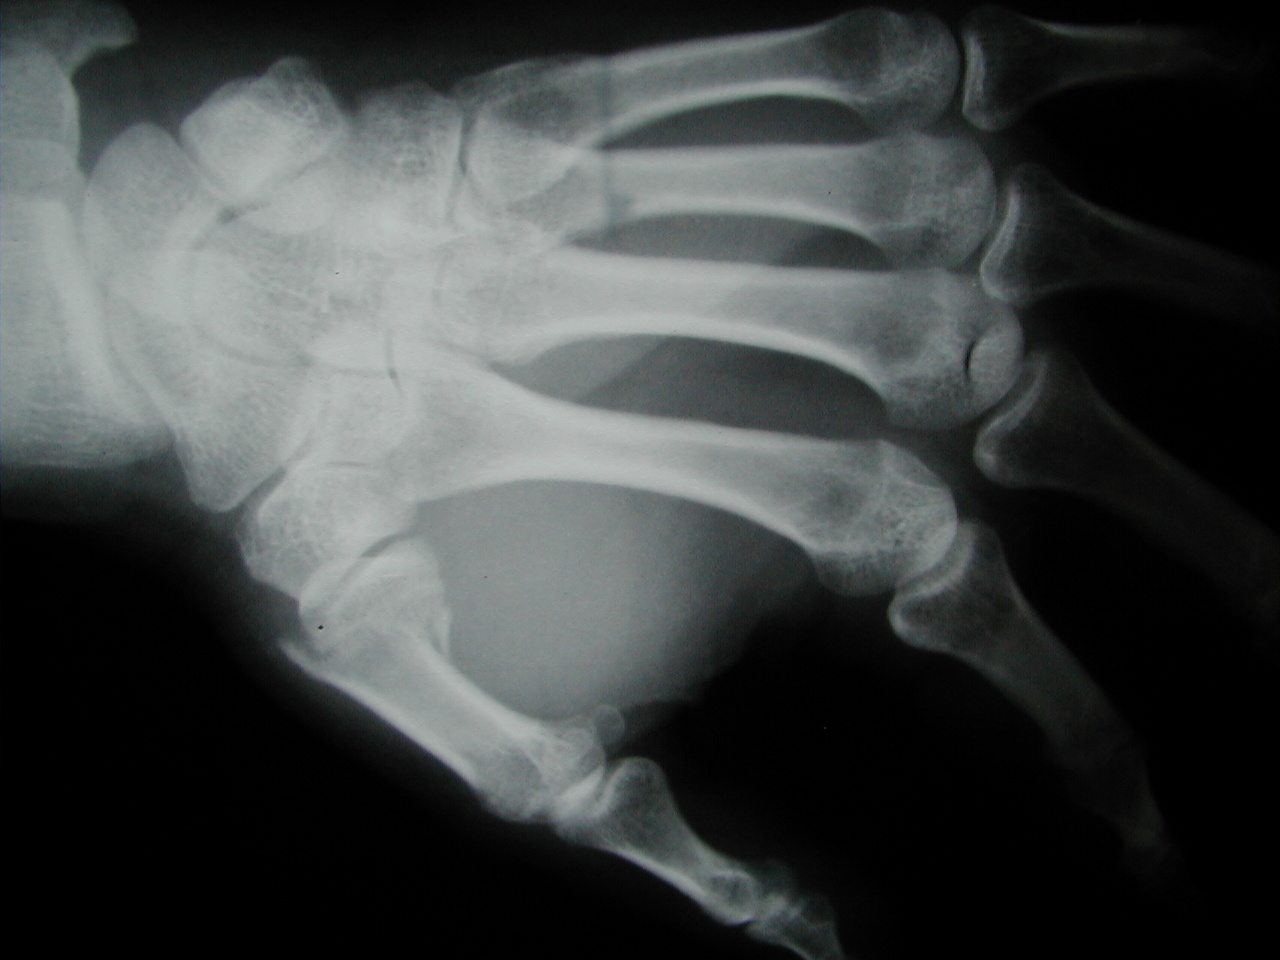

"Posilam muj prvni prispevek do sekce trauma. Suma sumarum: 2,5 hodky operace v plne narkoze, 2 sroubky v ruce, 5 stehu, 6x rentgen, 3 lahve kapacky a 3 sacky antibiotika do zily, 4 dni v nemocnici, 5 tydnu sadra... :-(

Diky vsem za sms prani. Ctibor"

Pro silné povahy přidávám detailní obrázky zranění: